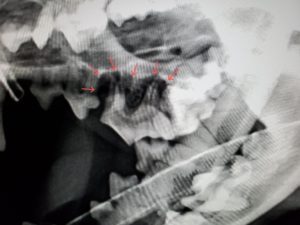

レントゲンでは赤矢印の部分に歯槽骨の吸収がみられました。